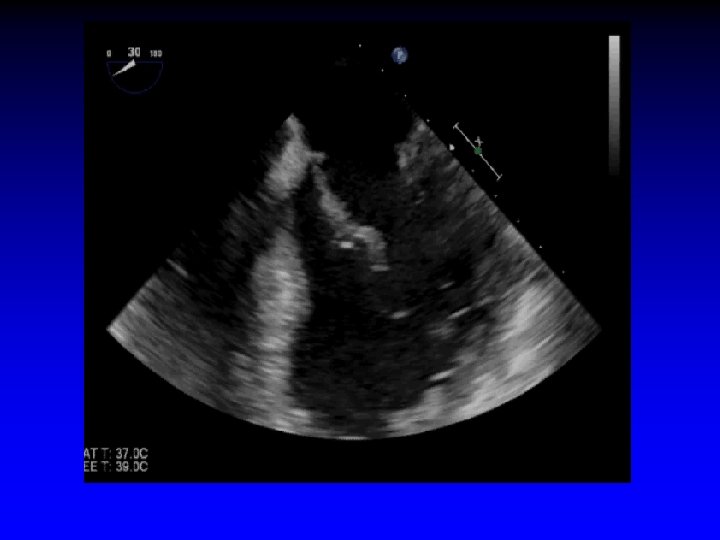

Case 1 Ruptured cords P 2

1. 6 cm +. . . + Gastric short-axis view (PSR view)